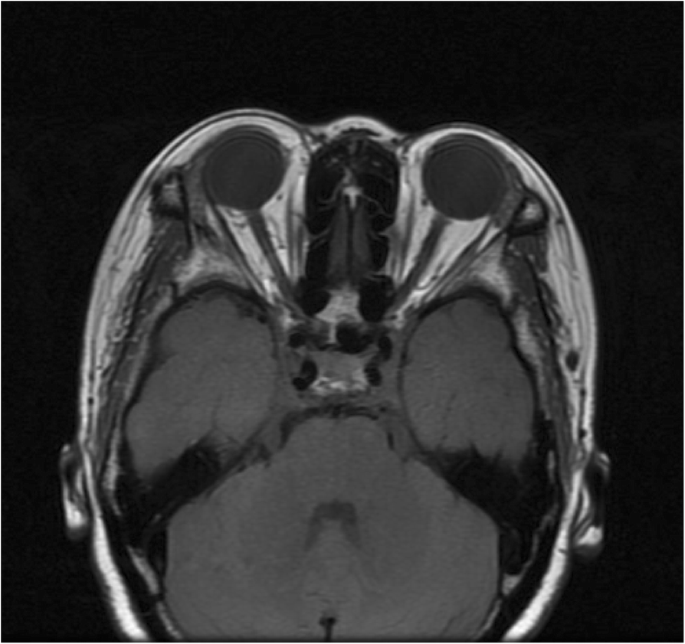

On follow-up examination, best-corrected visual acuities remained as 20/25 OD and 20/30 OS. Intraocular pressures were 21 mmHg OD and 19.3 mmHg OS. Ophthalmologic examination revealed bilateral exophthalmos, bulbar conjunctival edema and conjunctival congestion. Ocular alignment showed a limitation on elevation and abduction of both eyes. Corneas were clear with quiet anterior chamber. Both pupils were round, but there was an afferent pupillary defect in the left eye. Choroidal folds observed in the right eye, and optic disc swelling with lamellar hemorrhage around optic disc was found in the left eye (Fig. 2). MRI demonstrated orbital masses behind both globes (Fig. 3). T1-weighted contrast-enhanced imaging showed a predominantly low intensity signal with mildly heterogeneous in center of the masses. T2-weighted image demonstrated a heterogeneous hyperintense signal behind each globe. The patient received a number of blood tests, but no significant abnormality was detected. The C-reactive protein level and erythrocyte sedimentation rate were in normal range. The immunity tests showed negative in antistreptolysin-O, and rheumatoid factors (RF), including IgM-RF, IgA-RF, IgG-RF. The routine blood test also showed nothing abnormal, the results of white blood cell count, red blood cell count, haemoglobin, lymphocyte count, neutrophil count and platelet were all in normal range. The only finding was that eosinophil count was 0.72 × 10^9/L which was slightly above normal range.

a T1-weighted contrast-enhanced imaging showed a predominantly low intensity signal with mildly heterogeneous in center of the masses behind both globes (short arrows). b T2-weighted image demonstrated a heterogeneous hyper intense signal behind each globe (short arrows). c Coronal plane image illustrates hyperintense signal around both globes (short arrows)